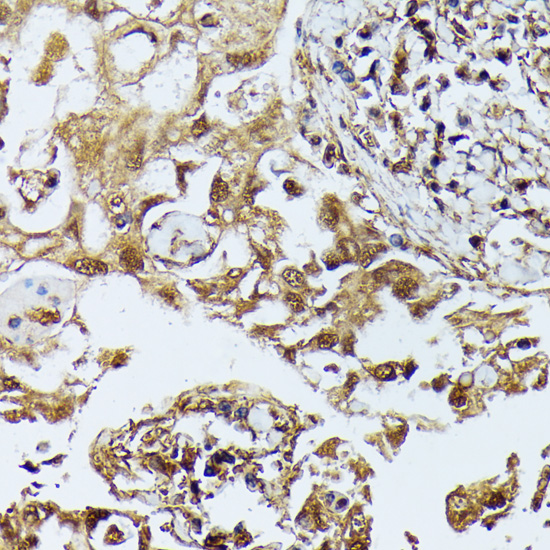

Immunohistochemistry of paraffin-embedded human lung cancer using DAPK3 antibody at dilution of 1:100 .